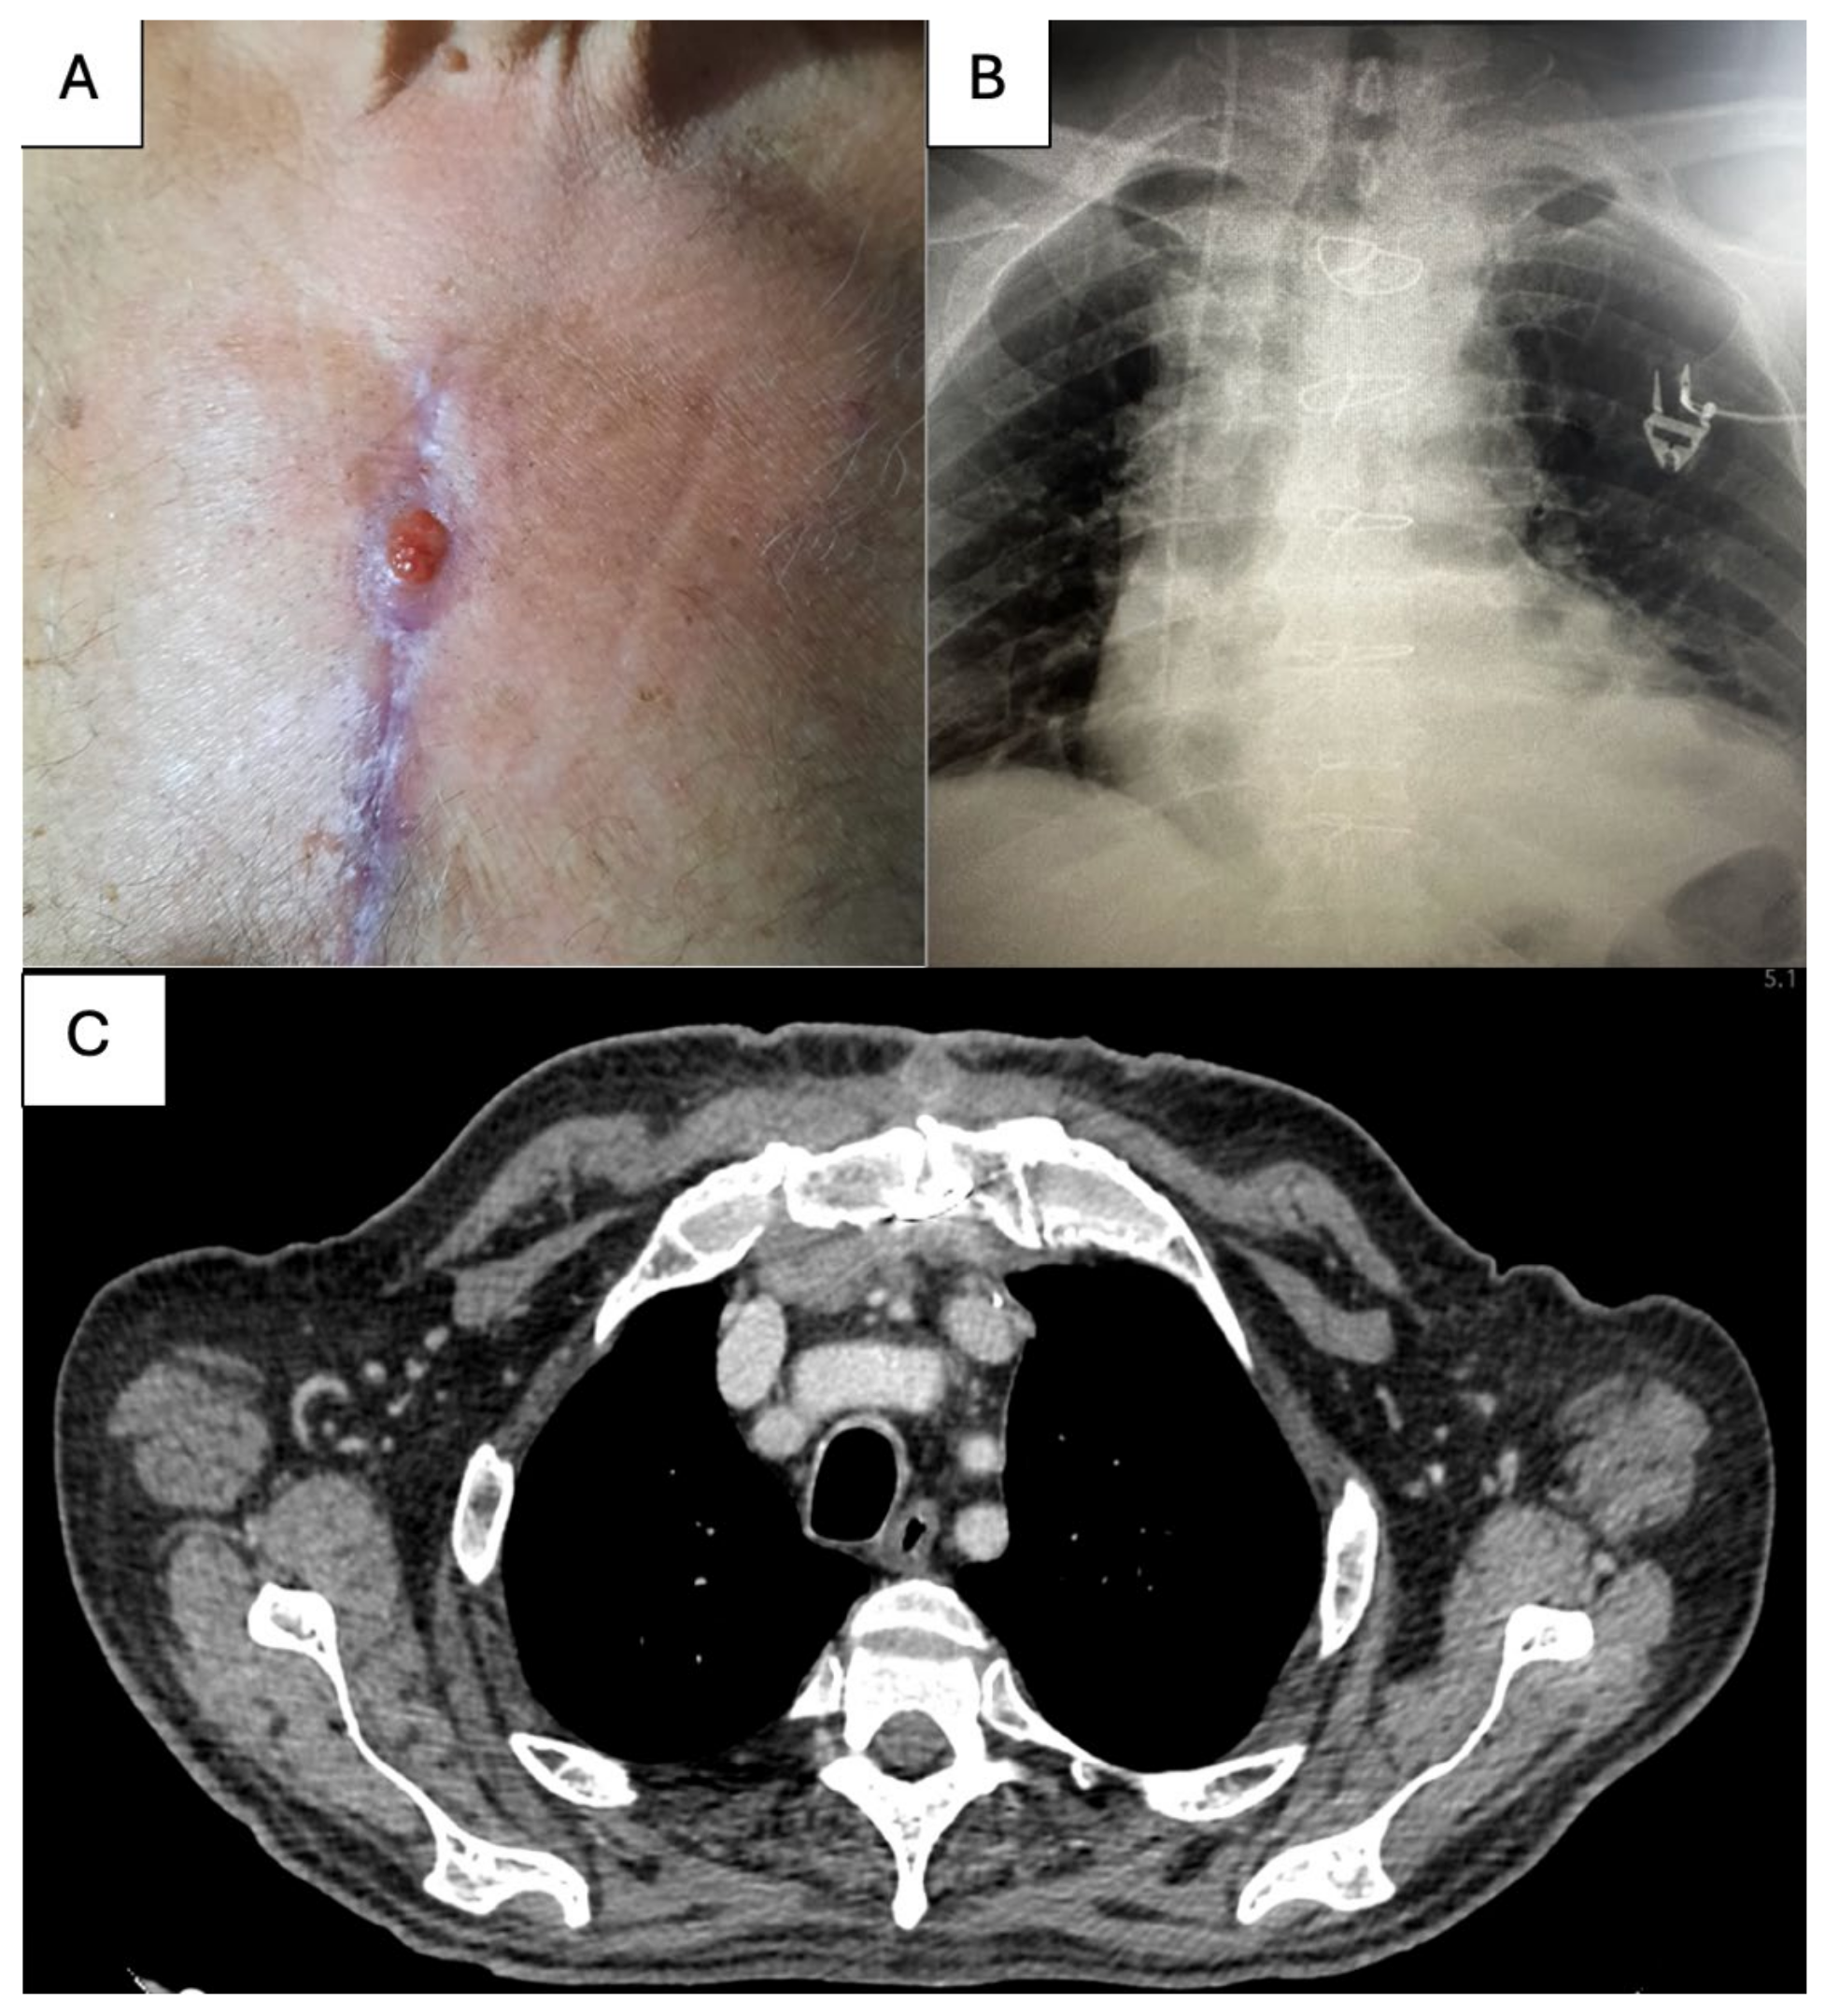

2. Case Report